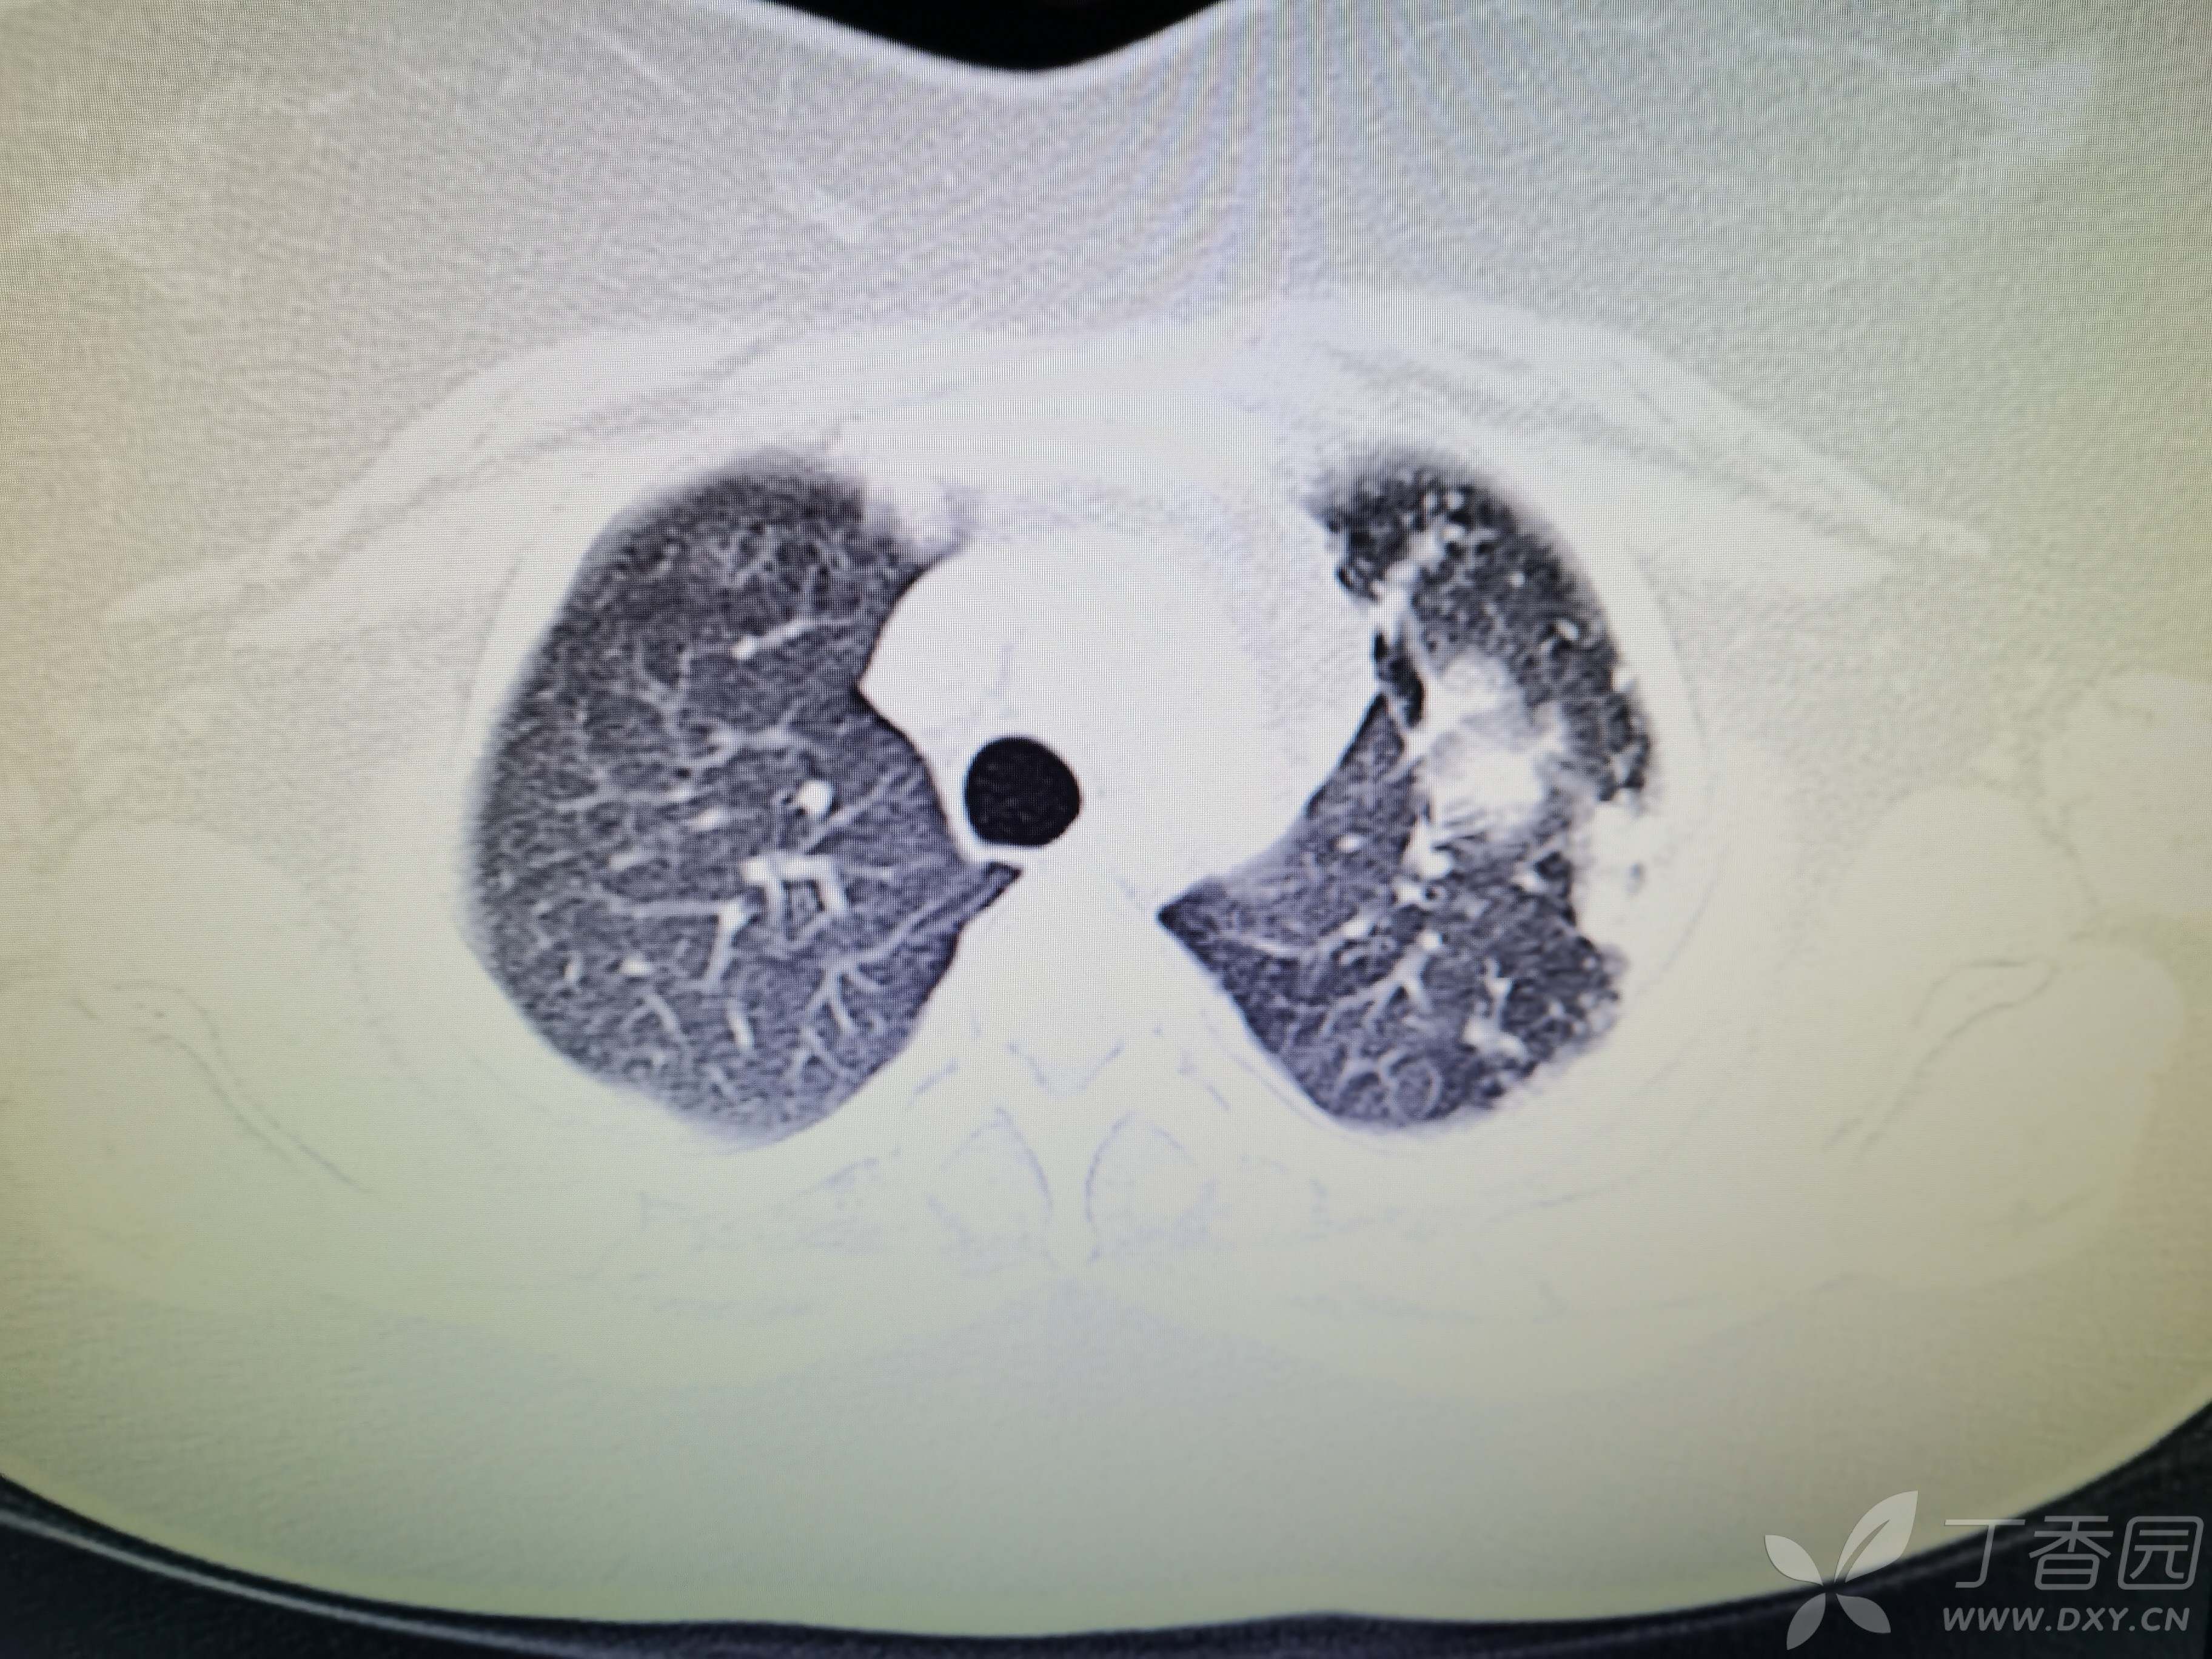

基本信息:女,三十几岁,印度人。。

胸部CT:

如题:猜肺部病灶病理。。